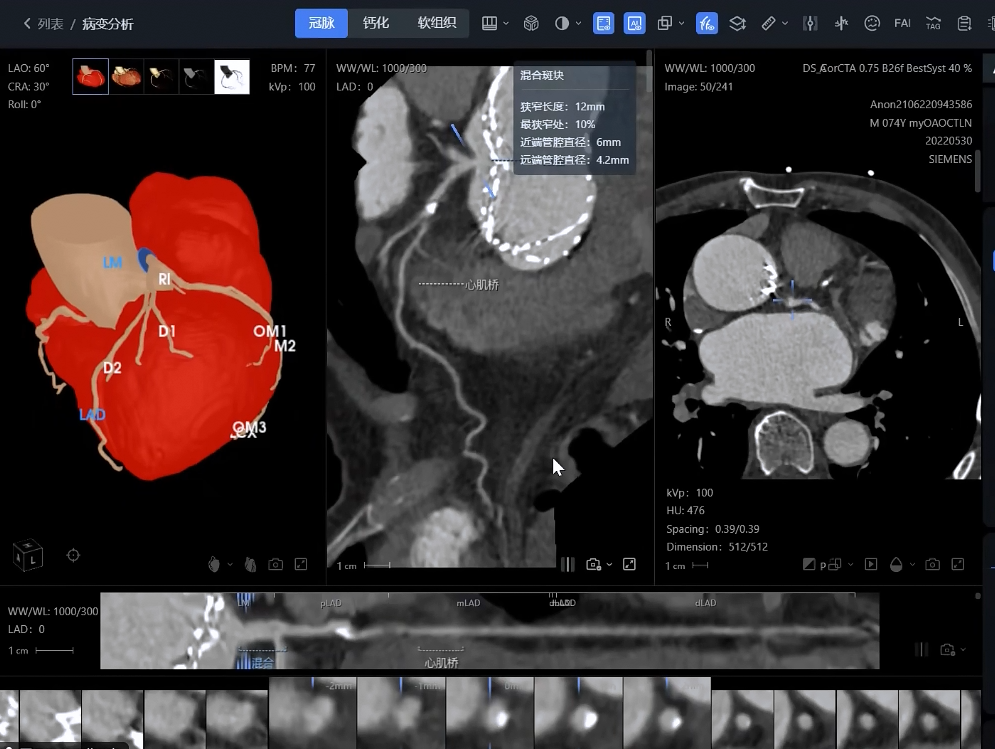

影像分析方面:系統(tǒng)能夠自動(dòng)處理心血管CTA、腦血管MRA、外周血管超聲等多模態(tài)影像數(shù)據(jù),精準(zhǔn)識(shí)別斑塊性質(zhì)、狹窄程度和病變范圍,生成結(jié)構(gòu)化報(bào)告。